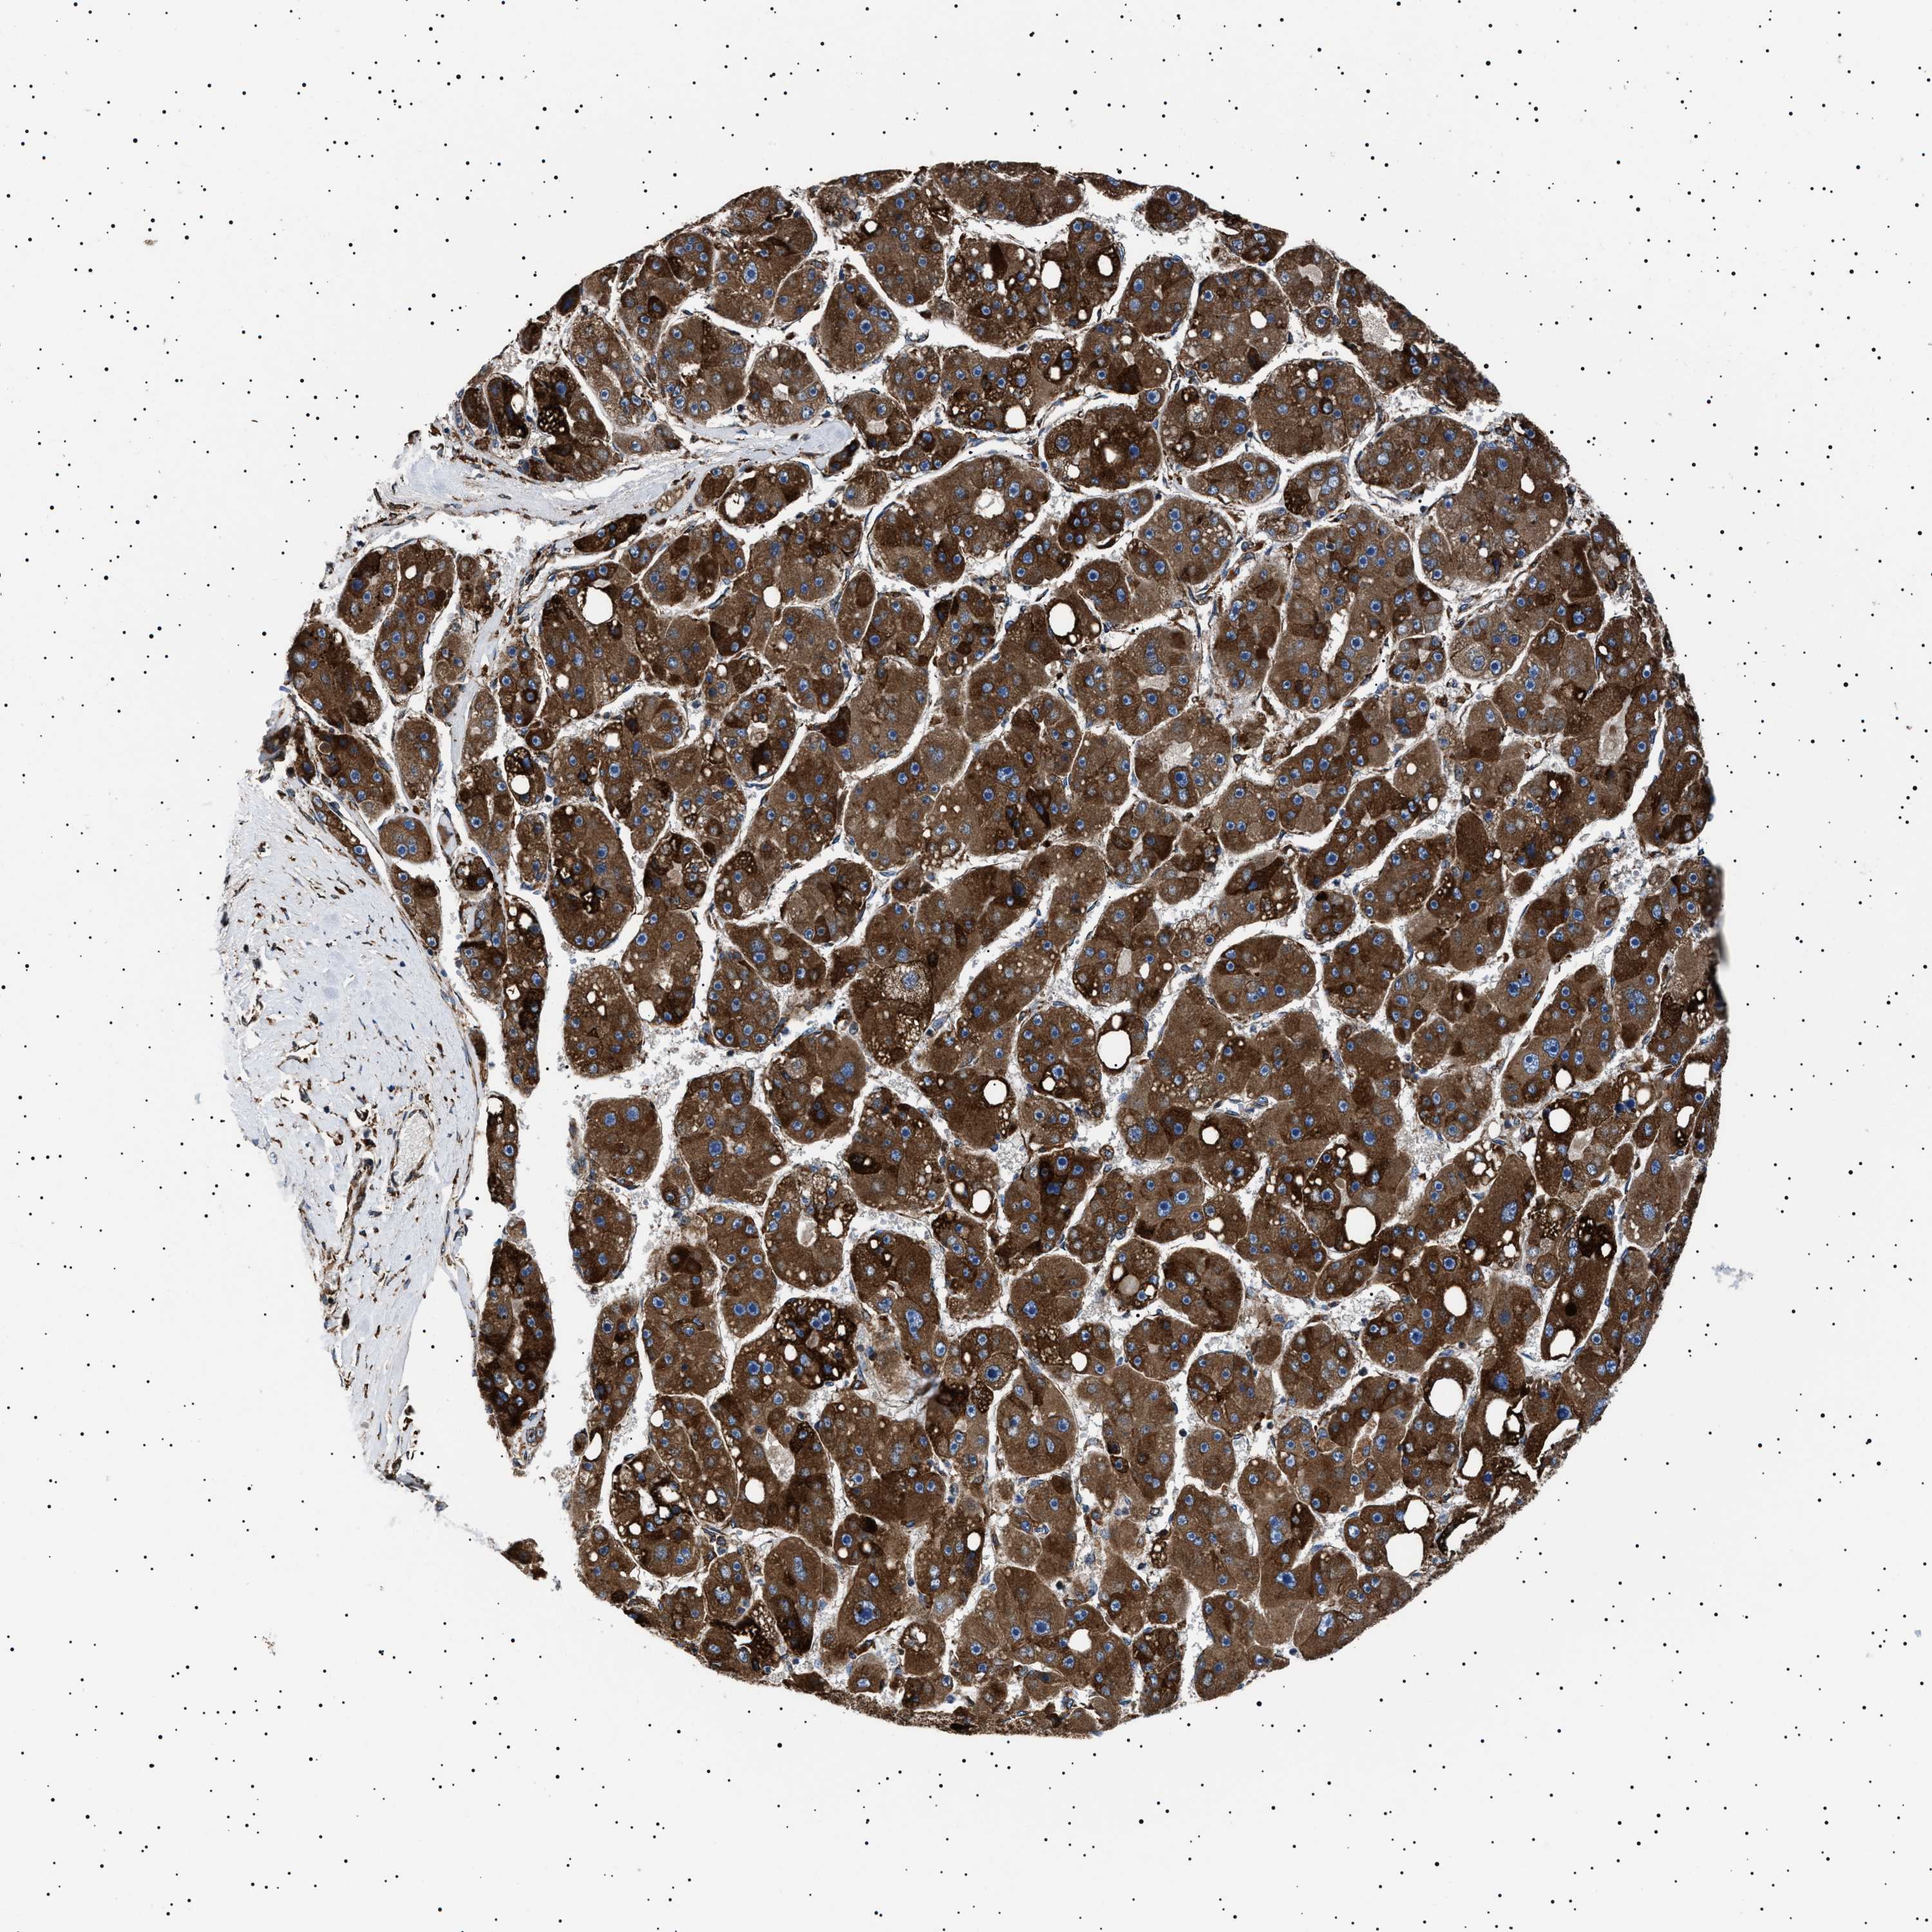

LIVER CANCER - Protein expressioni

A mouse-over function shows sample information and annotation data. Click on an image to view it in a full screen mode. Samples can be filtered based on level of antibody staining by selecting one or several of the following categories: high, medium, low and not detected. The assay and annotation is described here.

Note that samples used for immunohistochemistry by the Human Protein Atlas do not correspond to samples in the TCGA dataset.

Antibody stainingi

Antibody staining in the annotated cell types in the current human tissue is reported as not detected, low, medium, or high, based on conventional immunohistochemistry profiling in selected tissues. This score is based on the combination of the staining intensity and fraction of stained cells.

Each image is clickable and will lead to virtual microscopy that enables deeper exploration of all samples and also displays staining intensity scores, fraction scores and subcellular localization as well as patient and tissue information for each sample.

Antibody HPA001915

Antibody HPA021542

Staining

High

Medium

Low

Not detected

Intensity

Strong

Moderate

Weak

Negative

Quantity

>75%

75%-25%

<25%

None

Location

Nuclear

Cytoplasmic/membranous

Cytoplasmic/membranous,nuclear

Cholangiocarcinoma

Carcinoma, Hepatocellular, NOS